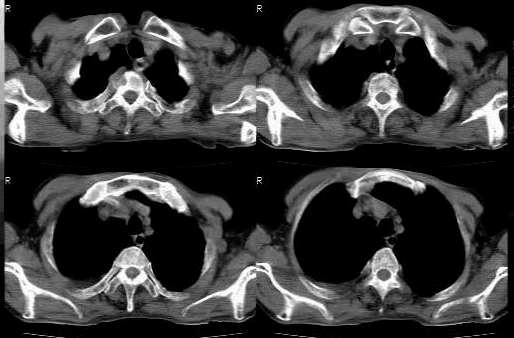

本例右胸腔巨块首先是定位问题,应定为前纵隔中、下区。理由:大部边缘光滑,部分mpi呈“长毛征”,mci呈凸出型,前联合线移向患侧。

其次是定性问题:本例征象:1 右侧胸腔巨块内见不规则钙化,征象同前述;2 左肺门肿块;3 肺内多发结节及支血束结节状改变;4 右上叶支气管受压无壁厚或阻塞;5 无肺纤维化表现;6 右侧胸液,心包无异常;7 骨质或腋窝无异常。结合老年患者,病史较长,以上征象集中在一起需鉴别于以下疾病:

1 前中、下区良性肿瘤恶性变伴肺内、胸膜及肺门转移及压迫性肺炎;此应放在最前面,如前所述,畸胎类肿瘤恶性变可能性较大,侵袭性胸腺瘤待排(mci多呈凹陷或平直型,前联合线多无异常改变),淋巴瘤基本不考虑。

2 纵隔和肺内、胸膜、肺门均为转移:纵隔肿块为转移癌但是病史不太支持,需进一步完善病史。

3 结节病:纵隔内为融合淋巴块,可有钙化,体积也可如此这大,肺内可有多发实质结节,也可单侧肺门淋巴结肿大和胸液,支血束结节状改变最为典型,但是病史较长者多有间质改变,请结合体检找有无皮下结节,此例绝不能排;